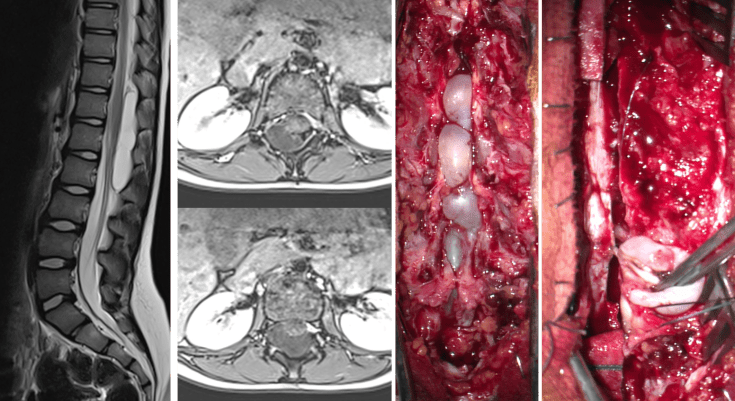

les méningocèles intrarachidiennes épidurales

parfois appelés improprement kystes arachnoïdiens spinaux épiduraux, elles sont souvent difficiles à distinguer des kystes arachnoïdiens intra-duraux, ces derniers étant également appelés méningocèles intra-durales, ce qui est fait pour accroître la confusion…

elles peuvent être découvertes fortuitement, ou être responsables d’une symptomatologie douloureuse ou neurologique (syndrome pyramidal).

situées le plus souvent à l’étage thoracique ou thoraco-lombaire, elles ont un pédicule de dure-mère, parfois plusieurs, qui la relient au contenu dural. elles peuvent s’intégrer dans un contexte génétique par mutation de Fox R2

l’indication chirurgicale est avant tout basée sur la clinique, cette chirurgie n’étant pas dénuée de risque neurologique ou rachidien.